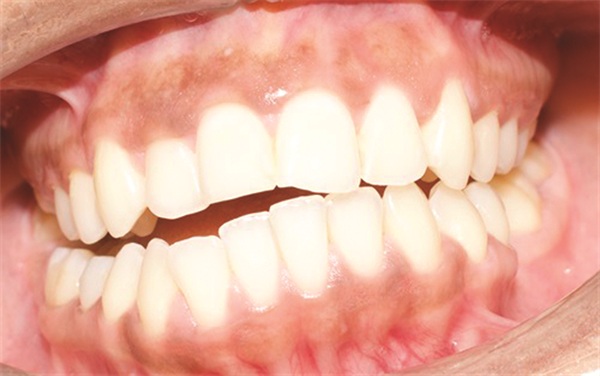

The diagnostic findings told a more complicated story. The patient presented with a skeletal Class II relationship, bilateral Class I molar and canine relationships, collapsed arches, and proclined incisors in both arches. Both midlines were shifted to the right. She also exhibited crossbite of the upper right first molar and upper right lateral incisor, a discrepancy between centric relation and centric occlusion, and a noticeable cant in the lower anterior segment. Her dental history included previous extractions of the upper right third molar and upper left second molar (Figs. 1–12).

Fig. 4